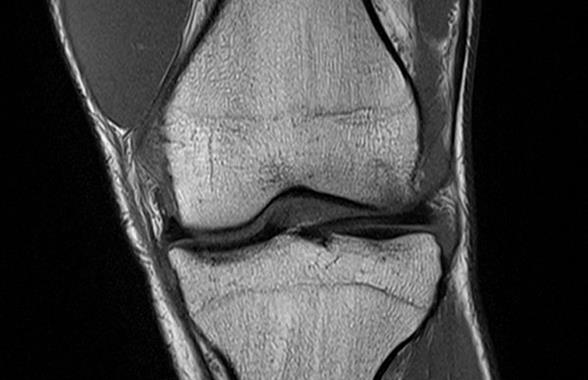

Die beste Neuigkeit vorweg: Fabian Hackhofer fällt nicht bis zum Saisonende aus, im Gegenteil: Er wird noch vor Dezember wieder spielen können, wenn sich nicht noch weitere Komplikationen einstellen. Die Visite am Sonntag bestätigte zwar das, was auf den Bildern der Magnetresonanztomographie deutlich zu sehen war, und zwar dass das vordere Kreuzband gerissen ist. Da aber im Knie keinerlei sonstige Verletzungen erkennbar sind und „Hacky“ bereits seit einiger Zeit völlig schmerzfrei ist, kann er mit einer maßgefertigten Karbonfiber-Orthese spielen, ohne dass ein nennenswertes Risiko besteht, das Knie weiter zu schädigen. Die Rückkehr nach einem gezielten Aufbautraining mit begleitender Physiotherapie ist bis spätestens Ende November geplant. Nach der Saison muss sich Hacky dann der Operation am Kreuzband unterziehen.